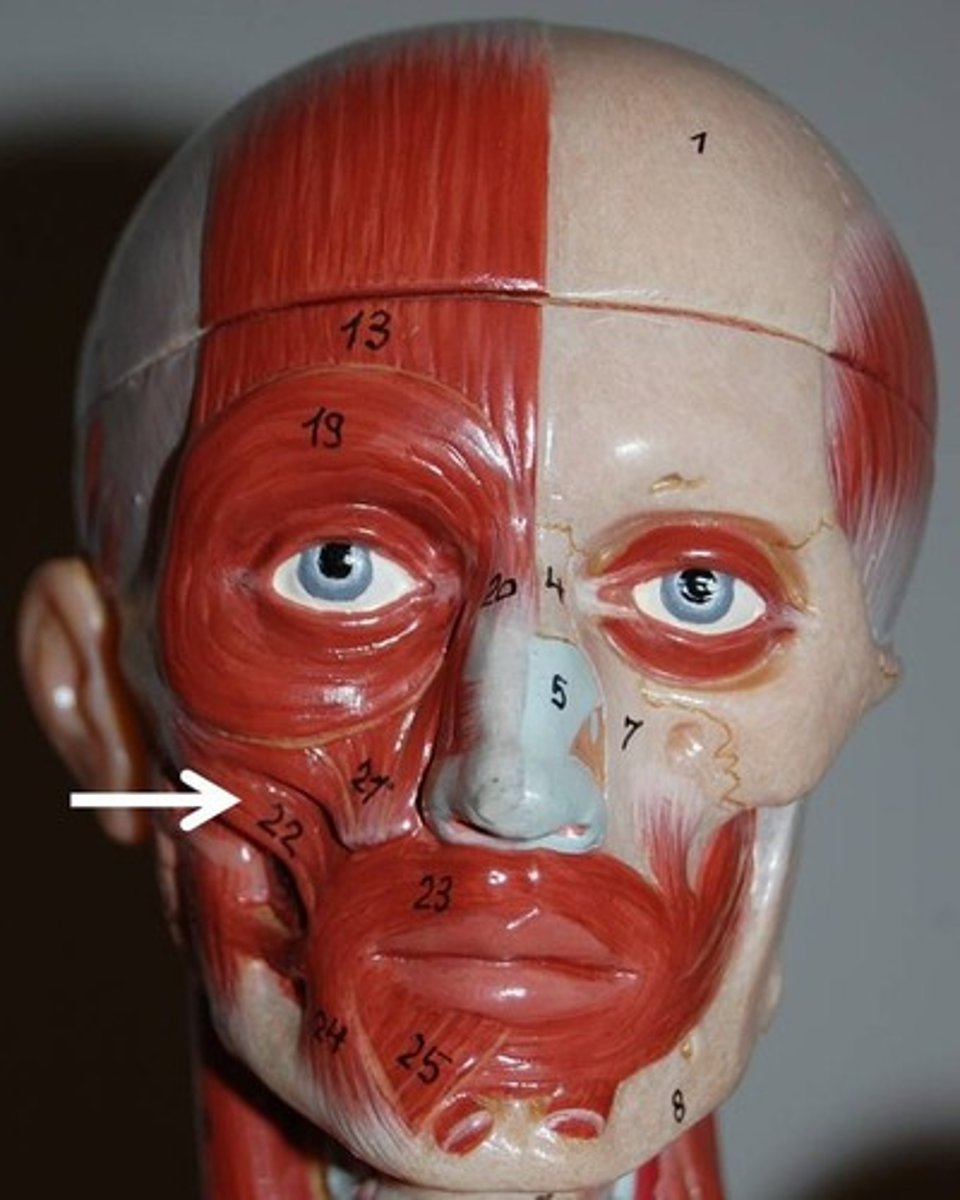

Buccinator

A flat, thin muscle in the wall of the cheek